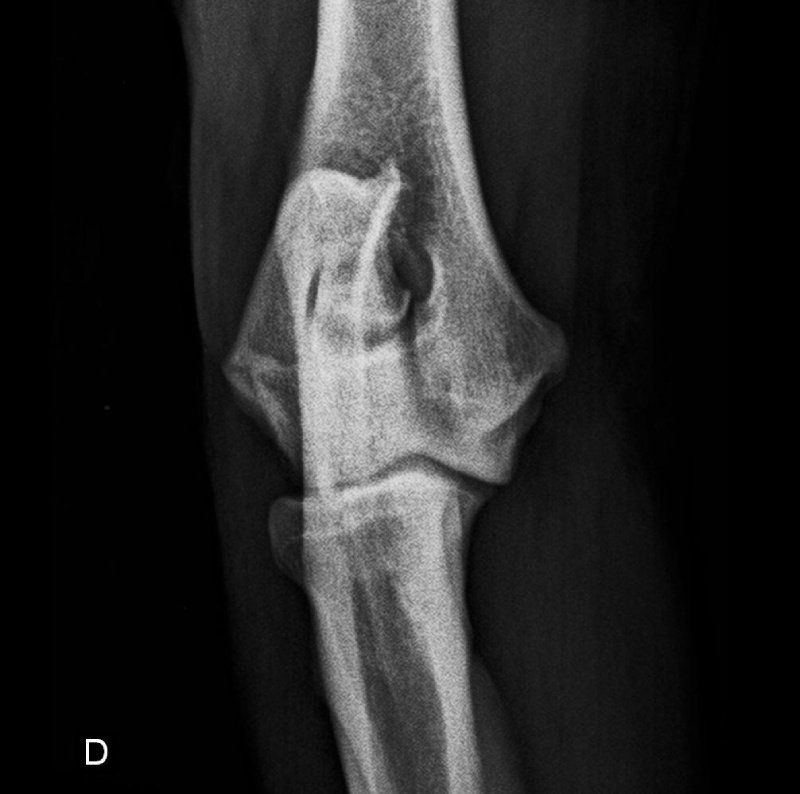

Offriamo i servizi che solo dei veri professionisti seri e qualificati del settore possono assicurare, così che i tuoi amici a quattro zampe possano godere sempre di buona salute. Ci occupiamo anche di eseguire studi radiografici ufficiali per le patologie scheletriche ereditarie, come ad esempio la displasia dell'anca o del gomito.